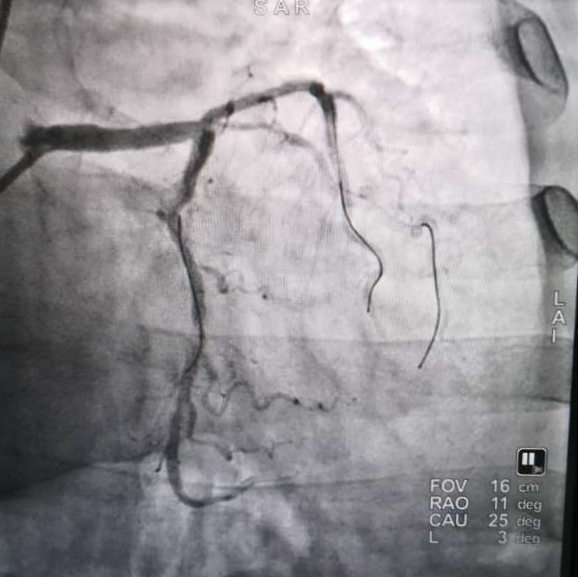

〖微创技术〗开启介入无植入时代——市医院心内科一病区成功开展药物球囊冠状动脉成形术

近日,我院心内科一病区团队成功为一位支架术后再次发生新病变患者实施了经皮冠状动脉药物球囊扩张成形术。该项技术的成功开展,填补了我院心脏病微创技术方面的空白,为广大心脏病患者提供了更加安全、有效的治疗手段。

经皮冠状动脉药物球囊扩张成形术,指经皮穿刺周围动脉将带有药物涂层球囊(DCB)的导管送入冠状动脉到达狭窄节段,扩张球囊,使狭窄管腔扩大,血流畅通,微小的药物载体覆盖在血管壁上,保证药物的持续释放,符合最佳药物代谢。支架内再狭窄是药物球囊首选适应症;其次,血管越细,植入支架后发生血栓和再狭窄风险较高时也适用于DCB;若出现分叉血管,也可通过边支药物球囊扩张,主支植入支架解决;对于部分高血压老年患者,无法耐受长期服药时,和一些外科手术患者需进行短期心脏调整,皆优选DCB。

相较于传统支架及药物涂层支架,DCB能够实现更好的侧支血管的血管开通;减少迟发型支架内血栓形成的风险;保留原有的解剖结构,尤其是一些小血管和血管分叉;广泛用于一些不能或不便于置入支架的病变处,比如一些小血管、支架内再狭窄以及一些分叉病变中侧支血管的治疗;且在一些扭曲的动脉血管中运送更加安全。